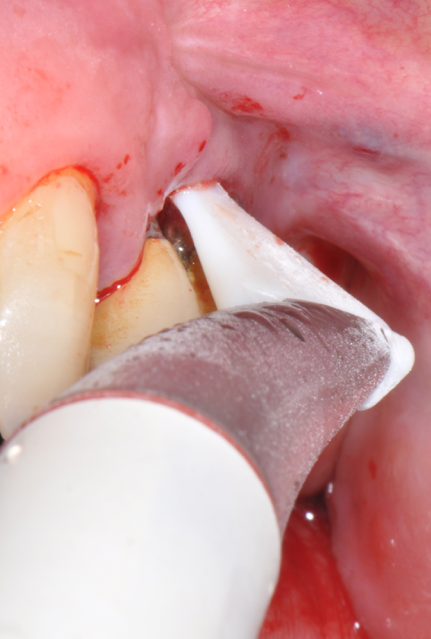

Fig.7: Pocket decontamination with erythritol powder conveyed by sub-gingival tip.

Fig.8: Implant surface debridment with piezo-ceramic device and PEEK tip.

So far, there is no scientific evidence supporting the efficacy of this coadjuvant. The tested protocol consist of a Multiple Anti Infective Non Surgical Therapy (MAINST) that involves the use topical 14% doxycycline to solve the peri-implantitis acute phase and, after 7 days, a session of Full Mouth Air Polishing Therapy (FM-EPAPT) through erythritol powder (Fig.7), a piezo-ceramic device with a PEEK tip (Fig.8), the curettage of internal pocket line (Fig.9) and a second application od Doxy. The patients were further followed with quarterly maintenance sessions carried on with the same FM-EPAPT protocol. Up to 12 months BOP and mean PD decreased significantly and successfully, accompanied by a gain of attachment level up to 12 months. The first case-series about MAINST is waiting to be published and the results are encouraging. Figure 10 and 11 show the healing at 6 and 12 months after MAINST protocol of the peri-implantitis case displayed at the beginning of this article (Fig.1,2,3,4) and figure 12-21 show a complete MAINST case.